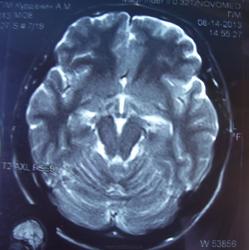

При изучении МРТ снимков головного мозга невролог указала на наличие маленьких очажков на коре головного мозга, порекомендовав обратиться за лечением к нейрохирургам. Голова также продолжает болеть, еще стали кисти рук неметь и прочие симптомы. Можете ли вы указать, имеются ли эти маленькие очажки на коре головного мозга и где именно?

Алексей, очагов достоверно не вижу, а вот на верхнечелюстную пазуху нужно обратить внимание-есть ее воспалительные изменения в виде утолщения слизистой.